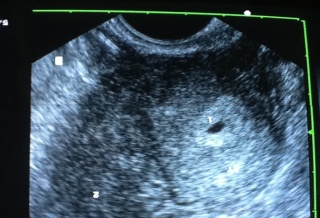

雙子宮雙胞胎 : 博元婦產科 試管嬰兒罕見案例 http://n.yam.com/uho/healthy/20121130/2012113001830...

雙子宮雙胞胎 試管嬰兒罕見案例 http://n.yam.com/uho/healthy/20121130/20121130018306.html 雙子宮雙胞胎 試管嬰兒罕見案例 ...